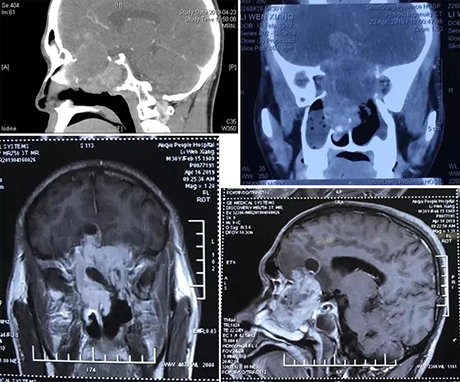

近日,1例侵袭颅鼻眶的巨大肿瘤手术在山东省立医院耳鼻喉科获得成功,病人康复出院。患者,男,30岁,影像学检查可见肿瘤向上侵犯前颅底,病人头疼,左眼视力仅能见光。如不及时切除,将会侵犯大脑、颈内动脉、颅神经,最终危及生命。颅脑底部的区域有供应人脑的主要血管和进出人脑的颅神经通过,手术风险非常高,稍有不慎就会造成大出血、颅神经损伤,甚至危及生命。长久以来鼻颅底贯通肿瘤的手术治疗一直困扰着耳鼻喉科及神经外科医生,单纯依靠一个科室很难做到颅鼻贯通肿瘤的彻底切除,因此多学科合作的需求日益迫切。

手术前影像